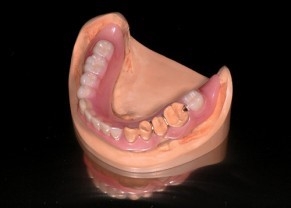

入れ歯(義歯)治療

ノンクラスプデンチャー

バネ部分がピンク色の樹脂のため、これまでの金属入れ歯に比べ目立ちにくい入れ歯です。

また、通常の入れ歯に比べ弾性がある強度の高い材料を使っているため、丈夫で薄くできるため違和感が少ないことが特徴です。

ストレスの少ない生活を送ることができます。

こんな入れ歯のお悩みの方には適しています

- 金属バネが目立って人前で大きく口を開けることができない

- 入れ歯に段差があってうまくしゃべれない

- 歯と入れ歯のすき間によく食べ物が詰まってしまう